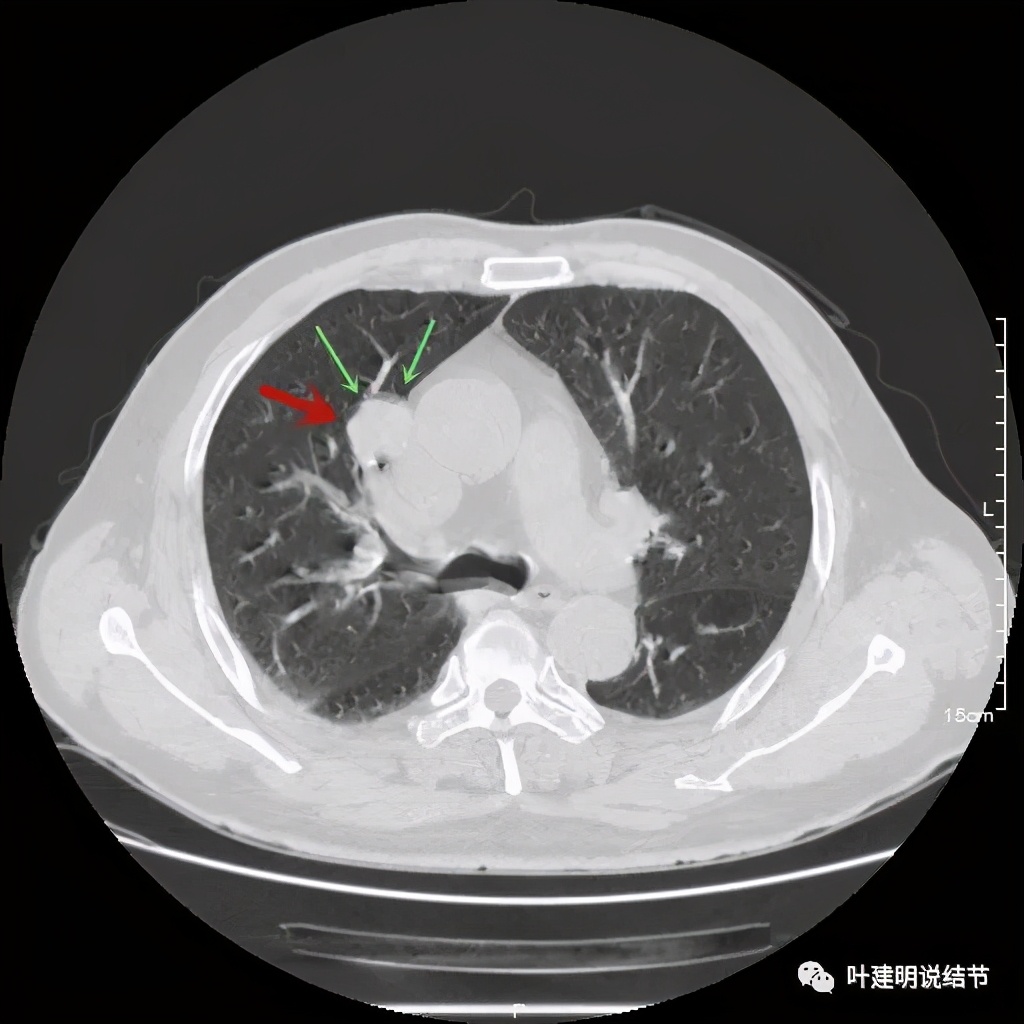

上图示病灶边缘过于光滑(绿色);局部有点状钙化(蓝色)

上图示病灶边缘过于光滑(绿色);血管贴边(桔色);

上图示病灶边缘过于光滑(绿色);血管贴边走行(桔色)

以上几图也示病灶边缘过光(绿色);血管贴边,感觉没受侵犯(桔色)

事前来看,达2.4厘米的不均质实性肿块,增强有轻度不均匀强化,血管贴边走行,支气管疑有截断,恶性不能除外,而且可能性较大。但现在经过手术已已经证实是错构瘤的情况下,我们回头来看,其实有许多不符合恶性的地方:

1、病灶的每个层面,边缘都过于光滑了。肺癌一般到这个大小总要有棘突、分叶、毛刺、牵拉周围胸膜等边缘异常的征象;

2、肿瘤大于2厘米以上,又紧贴血管,多有血管走行异常、受侵或血管进入等征象;